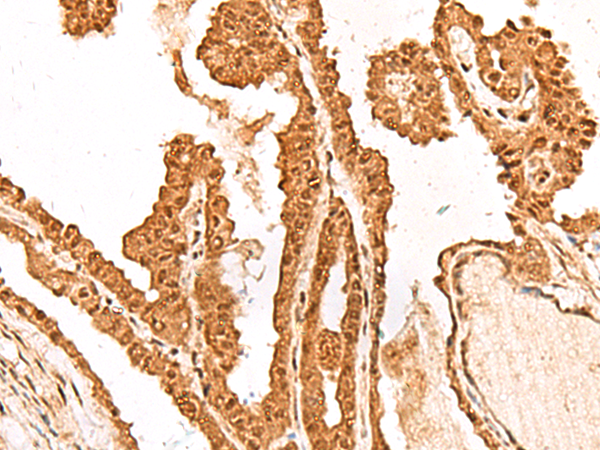

IHC (Immunohistochemistry)

(Figure 8. IHC analysis of FAM111B using anti-FAM111B antibody (AAA19994).FAM111B was detected in a paraffin-embedded section of human thyroid cancer tissue. Heat mediated antigen retrieval was performed in EDTA buffer (pH 8.0, epitope retrieval solution). The tissue section was blocked with 10% goat serum. The tissue section was then incubated with 2ug/ml rabbit anti-FAM111B Antibody (AAA19994) overnight at 4 degree C. Peroxidase Conjugated Goat Anti-rabbit IgG was used as secondary antibody and incubated for 30 minutes at 37 degree C. The tissue section was developed using HRP Conjugated Rabbit IgG Super Vision Assay Kit ( epitope retrieval solution). The tissue section was blocked with 10% goat serum. The tissue section was then incubated with 2ug/ml rabbit anti-FAM111B Antibody (AAA19994) overnight at 4 degree C. Peroxidase Conjugated Goat Anti-rabbit IgG was used as secondary antibody and incubated for 30 minutes at 37 degree C. The tissue section was developed using HRP Conjugated Rabbit IgG Super Vision Assay Kit ( epitope retrieval solution). The tissue section was blocked with 10% goat serum. The tissue section was then incubated with 2ug/ml rabbit anti-FAM111B Antibody (AAA19994) overnight at 4 degree C. Peroxidase Conjugated Goat Anti-rabbit IgG was used as secondary antibody and incubated for 30 minutes at 37 degree C. The tissue section was developed using HRP Conjugated Rabbit IgG Super Vision Assay Kit ( epitope retrieval solution). The tissue section was blocked with 10% goat serum. The tissue section was then incubated with 2ug/ml rabbit anti-FAM111B Antibody (AAA19994) overnight at 4 degree C. Peroxidase Conjugated Goat Anti-rabbit IgG was used as secondary antibody and incubated for 30 minutes at 37 degree C. The tissue section was developed using HRP Conjugated Rabbit IgG Super Vision Assay Kit ( epitope retrieval solution). The tissue section was blocked with 10% goat serum. The tissue section was then incubated with 2ug/ml rabbit anti-FAM111B Antibody (AAA19994) overnight at 4 degree C. Peroxidase Conjugated Goat Anti-rabbit IgG was used as secondary antibody and incubated for 30 minutes at 37 degree C. The tissue section was developed using HRP Conjugated Rabbit IgG Super Vision Assay Kit ( epitope retrieval solution). The tissue section was blocked with 10% goat serum. The tissue section was then incubated with 2ug/ml rabbit anti-FAM111B Antibody (AAA19994) overnight at 4 degree C. Peroxidase Conjugated Goat Anti-rabbit IgG was used as secondary antibody and incubated for 30 minutes at 37 degree C. The tissue section was developed using HRP Conjugated Rabbit IgG Super Vision Assay Kit (Lane 2: human Hacat whole cell lysates,Lane 3: human RT4 whole cell lysates,Lane 4: human U2OS whole cell lysates.After electrophoresis, proteins were transferred to a nitrocellulose membrane at 150 mA for 50-90 minutes. Blocked the membrane with 5% non-fat milk/TBS for 1.5 hour at RT. The membrane was incubated with rabbit anti-FAM111B antigen affinity purified polyclonal antibody (#AAA19994) at 0.5ug/mL overnight at 4 degree C, then washed with TBS-0.1%Tween 3 times with 5 minutes each and probed with a goat anti-rabbit IgG-HRP secondary antibody at a dilution of 1:5000 for 1.5 hour at RT. The signal is developed using an Enhanced Chemiluminescent detection (ECL) kit (Lane 2: human Hela whole cell lysates,Lane 3: human MCF-7 whole cell lysates.After electrophoresis, proteins were transferred to a nitrocellulose membrane at 150 mA for 50-90 minutes. Blocked the membrane with 5% non-fat milk/TBS for 1.5 hour at RT. The membrane was incubated with rabbit anti-FAM111B antigen affinity purified polyclonal antibody (#AAA19994) at 0.5ug/mL overnight at 4 degree C, then washed with TBS-0.1%Tween 3 times with 5 minutes each and probed with a goat anti-rabbit IgG-HRP secondary antibody at a dilution of 1:5000 for 1.5 hour at RT. The signal is developed using an Enhanced Chemiluminescent detection (ECL) kit with Tanon 5200 system. A specific band was detected for FAM111B at approximately 85 kDa. The expected band size for FAM111B is at 85 kDa.)